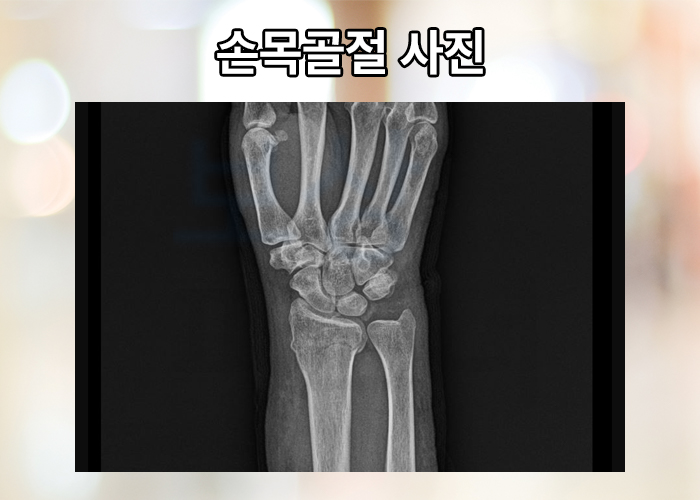

기록적인 한파와 연이은 폭설로 빙판길 미끄러짐 사고 급증하고 있는데요,

나도 모르게 신체를 보호하기 위해

손을 바닥으로 뻗는 행위가

손목 골절을 유발 할 수 있습니다.

위와 같은 사고 경위로 발생하는 골절의 양상을 대부분 콜리스 골절 이라고도 하는데요, 손목이 골절되었을 경우 진단서 및 영상판독지를 보험회사에 제출하면 받을 수 있습니다. 골절 치료 목적으로 핀 삽입술 또는 금속판 고정술 등의 골절 치료 수술을 받은 경우 보험금을 받을 수 있습니다.